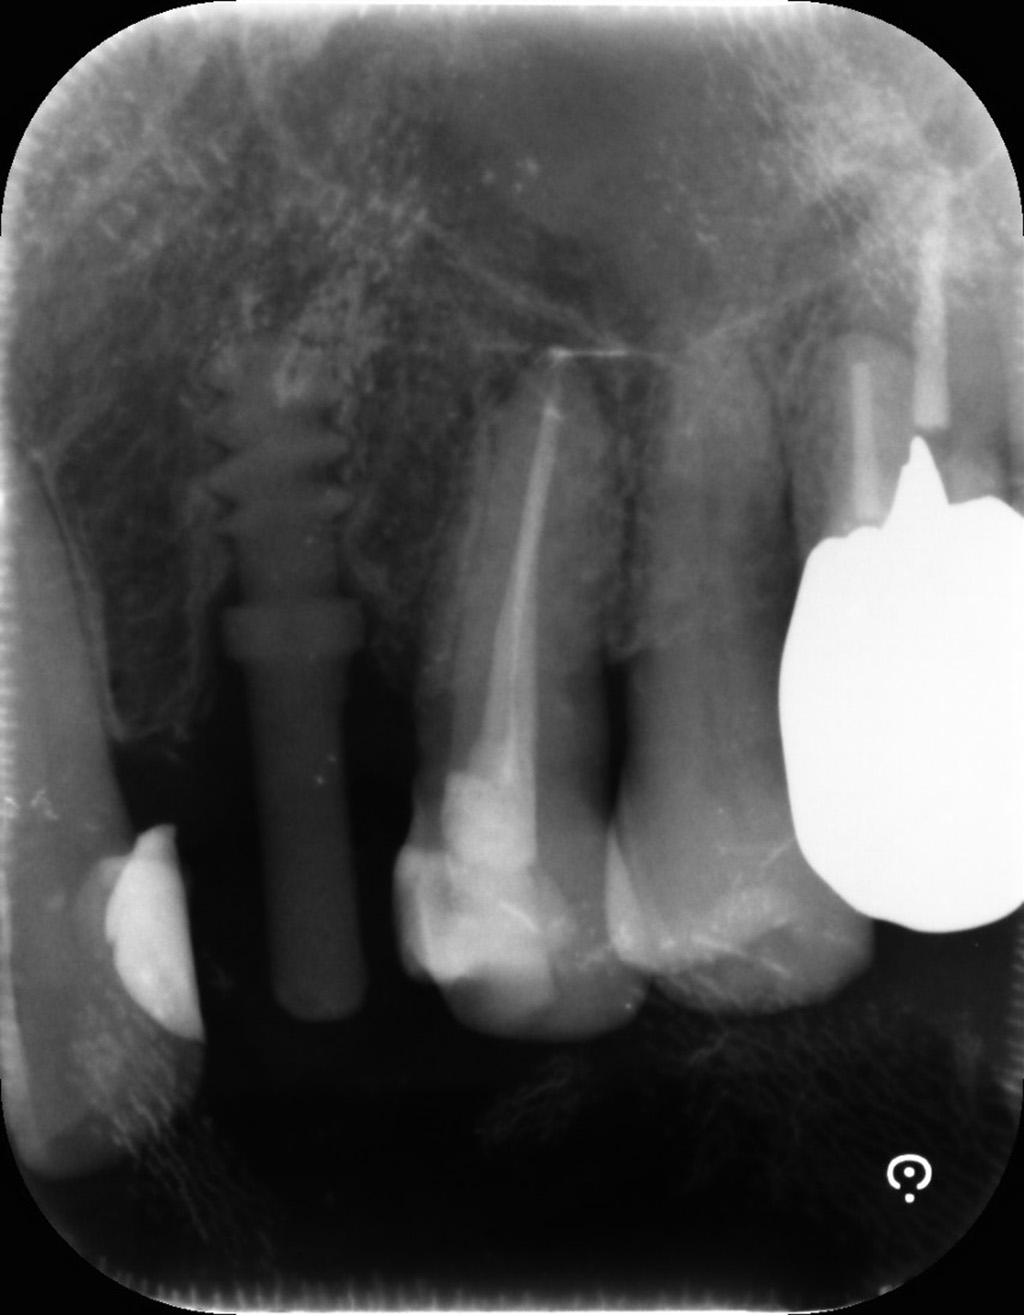

そして1年に1回は経過を確認するためにX線写真の撮影も必要ということで、デンタルを撮影してみました。

レントゲン上には、動画内で指摘されていたお椀状の骨吸収がある!

と今の私は読み取ることができます。

お椀状の骨吸収はインプラント周囲炎の指標です。

↑実際のデンタルです

初診時のパノラマから骨吸収の変化はありませんでした。

『ベースラインと比較して変化はなし』であるという気付きと、初診時から周囲炎の特徴を示していたが、見つけられていなかったことに気が付きました。